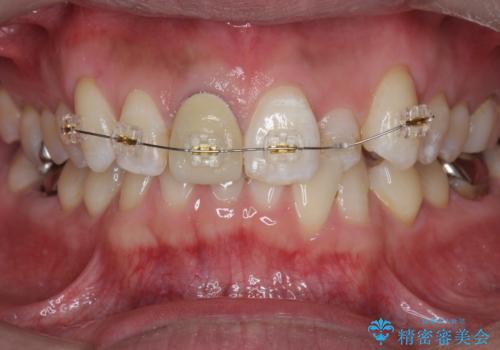

- インビザライン +部分ワイヤー矯正

- 10ヶ月

奥に位置している前歯を部分ワイヤー矯正ののちマウスピース矯正インビザラインで並べ、矯正治療後に審美的なジルコニアクラウンを作製していきます。